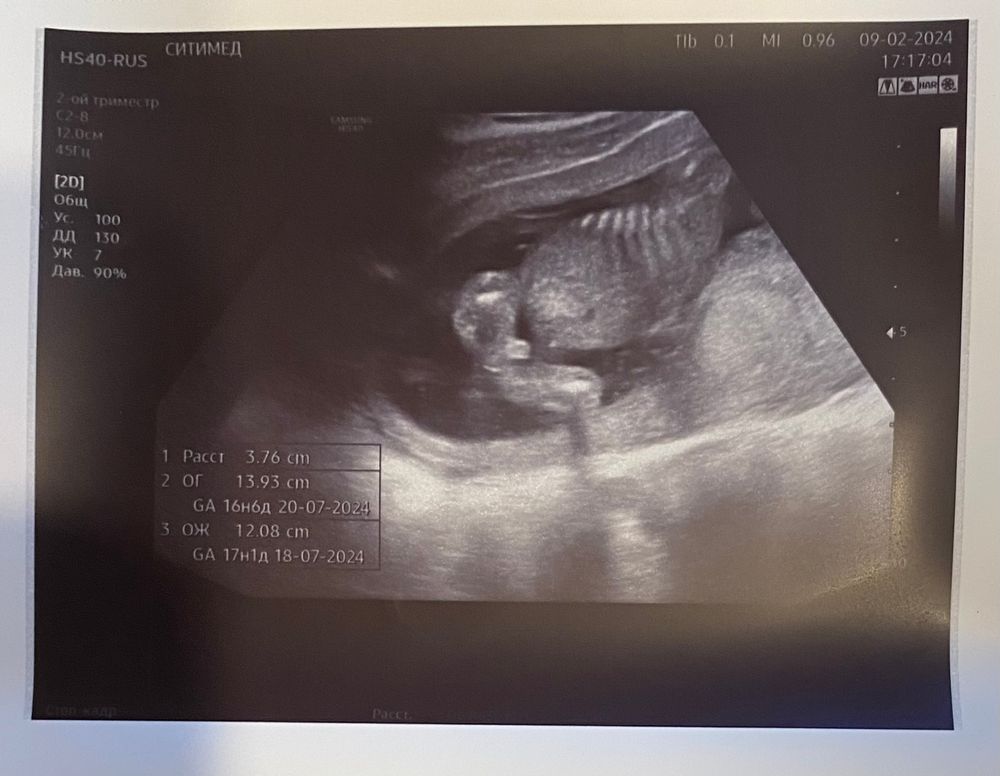

Всем привет!Вчера были на узи, срок 16.3 дня, врач говорила не пойму , и не девочку и на мальчика, все держит между ног и пуповину и руки.Но мне кажется по фото там явно мальчик.